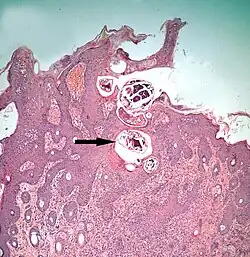

The diagram Mite infestation sites on skin shows where typical infestations of different taxonomic groups mites on livestock animals occur on or in the host's skin.[9] The position of these mites in relation to the skin or other organs is crucial for their feeding and also for their veterinary diagnosis and options for treatment. The mites either feed on the tissues of the skin using penetrating mouthparts or on the inflammatory exudate that results from the action of the mouthparts and saliva of the mites on the skin.[12] Demodectic mites have mouthparts adapted to penetrate and suck out the contents of individual cells of hair follicles.[13] It is usual for all active stages of the mite lifecycle to feed as parasites, but the trombiculid mites are an exception. Most of the parasitic mites do not feed directly on blood, but the dermanyssid mites and larval trombiculid mites directly suck up capillary blood as their exclusive food. The tube through which food is ingested and saliva excreted during feeding is formed in most mites by apposing the sheath that contains the chelicerae against the hypostome. However, the trombiculids are an exception. Some species of mites (Analgidae) have adapted to feeding on keratin and skin debris amongst the feathers of birds, and other species have adapted to feed directly on internal tissues such as air-sacs or lungs (Cytoditidae and Laminosioptidae). Psoroptic mites feed superficially at the stratum corneum; the photograph of a histological section of skin infested with Psoroptes ovis, and the photograph of the surface of a host's skin infested with P. ovis looking like white dots, show this type of feeding. Sarcoptic mites feed by burrowing within the living layers of the epidermis, mainly stratum spinosum. Demodectic mites feed in a position technically external to the skin, between the epidermis and the hair shaft in hair follicles. Dermanyssid and trombiculid mites feed whilst external to the skin by piercing the skin with, respectively, their chelicerae or a stylostome feeding tube. Mites at other sites feed by using their chelicerae to scrape either at the skin surface, or at base of feather, or to penetrate and scrape at internal tissue such as air-sac or lung.

The clinical manifestation of infestation with psoroptic mites is usually called mange and sometimes scabies, but the skin disease of sheep caused by Psoroptes ovis is often known locally as sheep scab. This species may affect its hosts severely enough to reduce their gain in weight.[25] Costs to farmers of controlling sheep-scab in Britain were at £8 million (US$12 million) annually in 2005.[26] Transmission between hosts is readily accomplished by contagion during flocking contact and also on fomites such as scraps of sheep's wool because these relatively large and robust mites can survive for one to two weeks off their host. Psoroptes ovis infests the superficial layers of the skin. Irritation of the outer skin by the mite's mouthparts and saliva results in a complex form of cutaneous hypersensitivity and inflammatory exudation of serum and fresh cells. The mites feed on this moist exudate.[27] The skin loses its hair (depilation) at the sites of infestation and this may be extensive. As a result of the movement of the mites into areas of fresh skin, large scabs accumulate on the raw skin left behind. The mites cause intense pruritus (itching). In cases of heavy infestations, the host grooms compulsively, aggravating the depilation, and it may become mentally distressed.[28] Psoroptes ovis infests sheep worldwide and can be a serious welfare and animal-production problem for sheep farmers. Infestations of cattle with mites of the similar genus Chorioptes, in combination with Sarcoptes mite infestation, has been shown to cause a failure to gain body weight by 15.5 to 37.2 kilograms (34+1⁄8 to 82 lb) over a two-month period compared to cattle without the mites.[29]